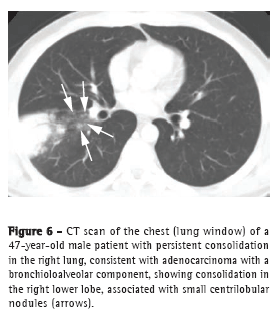

ConsolidationThe consolidation pattern accounts for up to 30% of all BAC cases, being more common in the mucinous variant.(3) This pattern has also been described as the pneumonic form of BAC.(18) Given the difficulty in distinguishing this BAC pattern from that of infectious pneumonia, there is often a delay in diagnosis. Some findings, such as the angiogram sign, air bronchograms, ground-glass opacities, and air-space nodules (Figure 6), can be observed in BAC and in lobar pneumonia.(3,19) Lymph node enlargement and pleural effusion can also be found in both entities.(16) Parenchymal consolidation that remains unresolved after treatment should raise the hypothesis of lung cancer.(2,3,18)